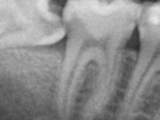

* Съвременно кореново(ендодонтско) лечение:

* Машинна никел-титанова обработка на кореновите канали

* Запълване с топла вертикална кондензация

* Прелекуване на ендодонтски лекувани зъби